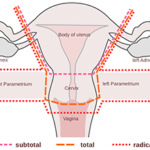

Dos and Don’ts Post Hysterectomy

Author –Dr Preety Aggarwal MBBS, DGO, DNB, Medical Director (Gurgaon)- Obstetrics and Gynaecology. Dos and Don’ts Post Hysterectomy Hysterectomy or removal of the uterus, whether laparoscopic or abdominal, is one of the common surgeries today. According to Dr Preety Aggarwal, MBBS, DGO, DNB, Medical Director (Gurgaon)- Obstetrics and Gynaecology, the surgery is performed to remove fibroids from […]